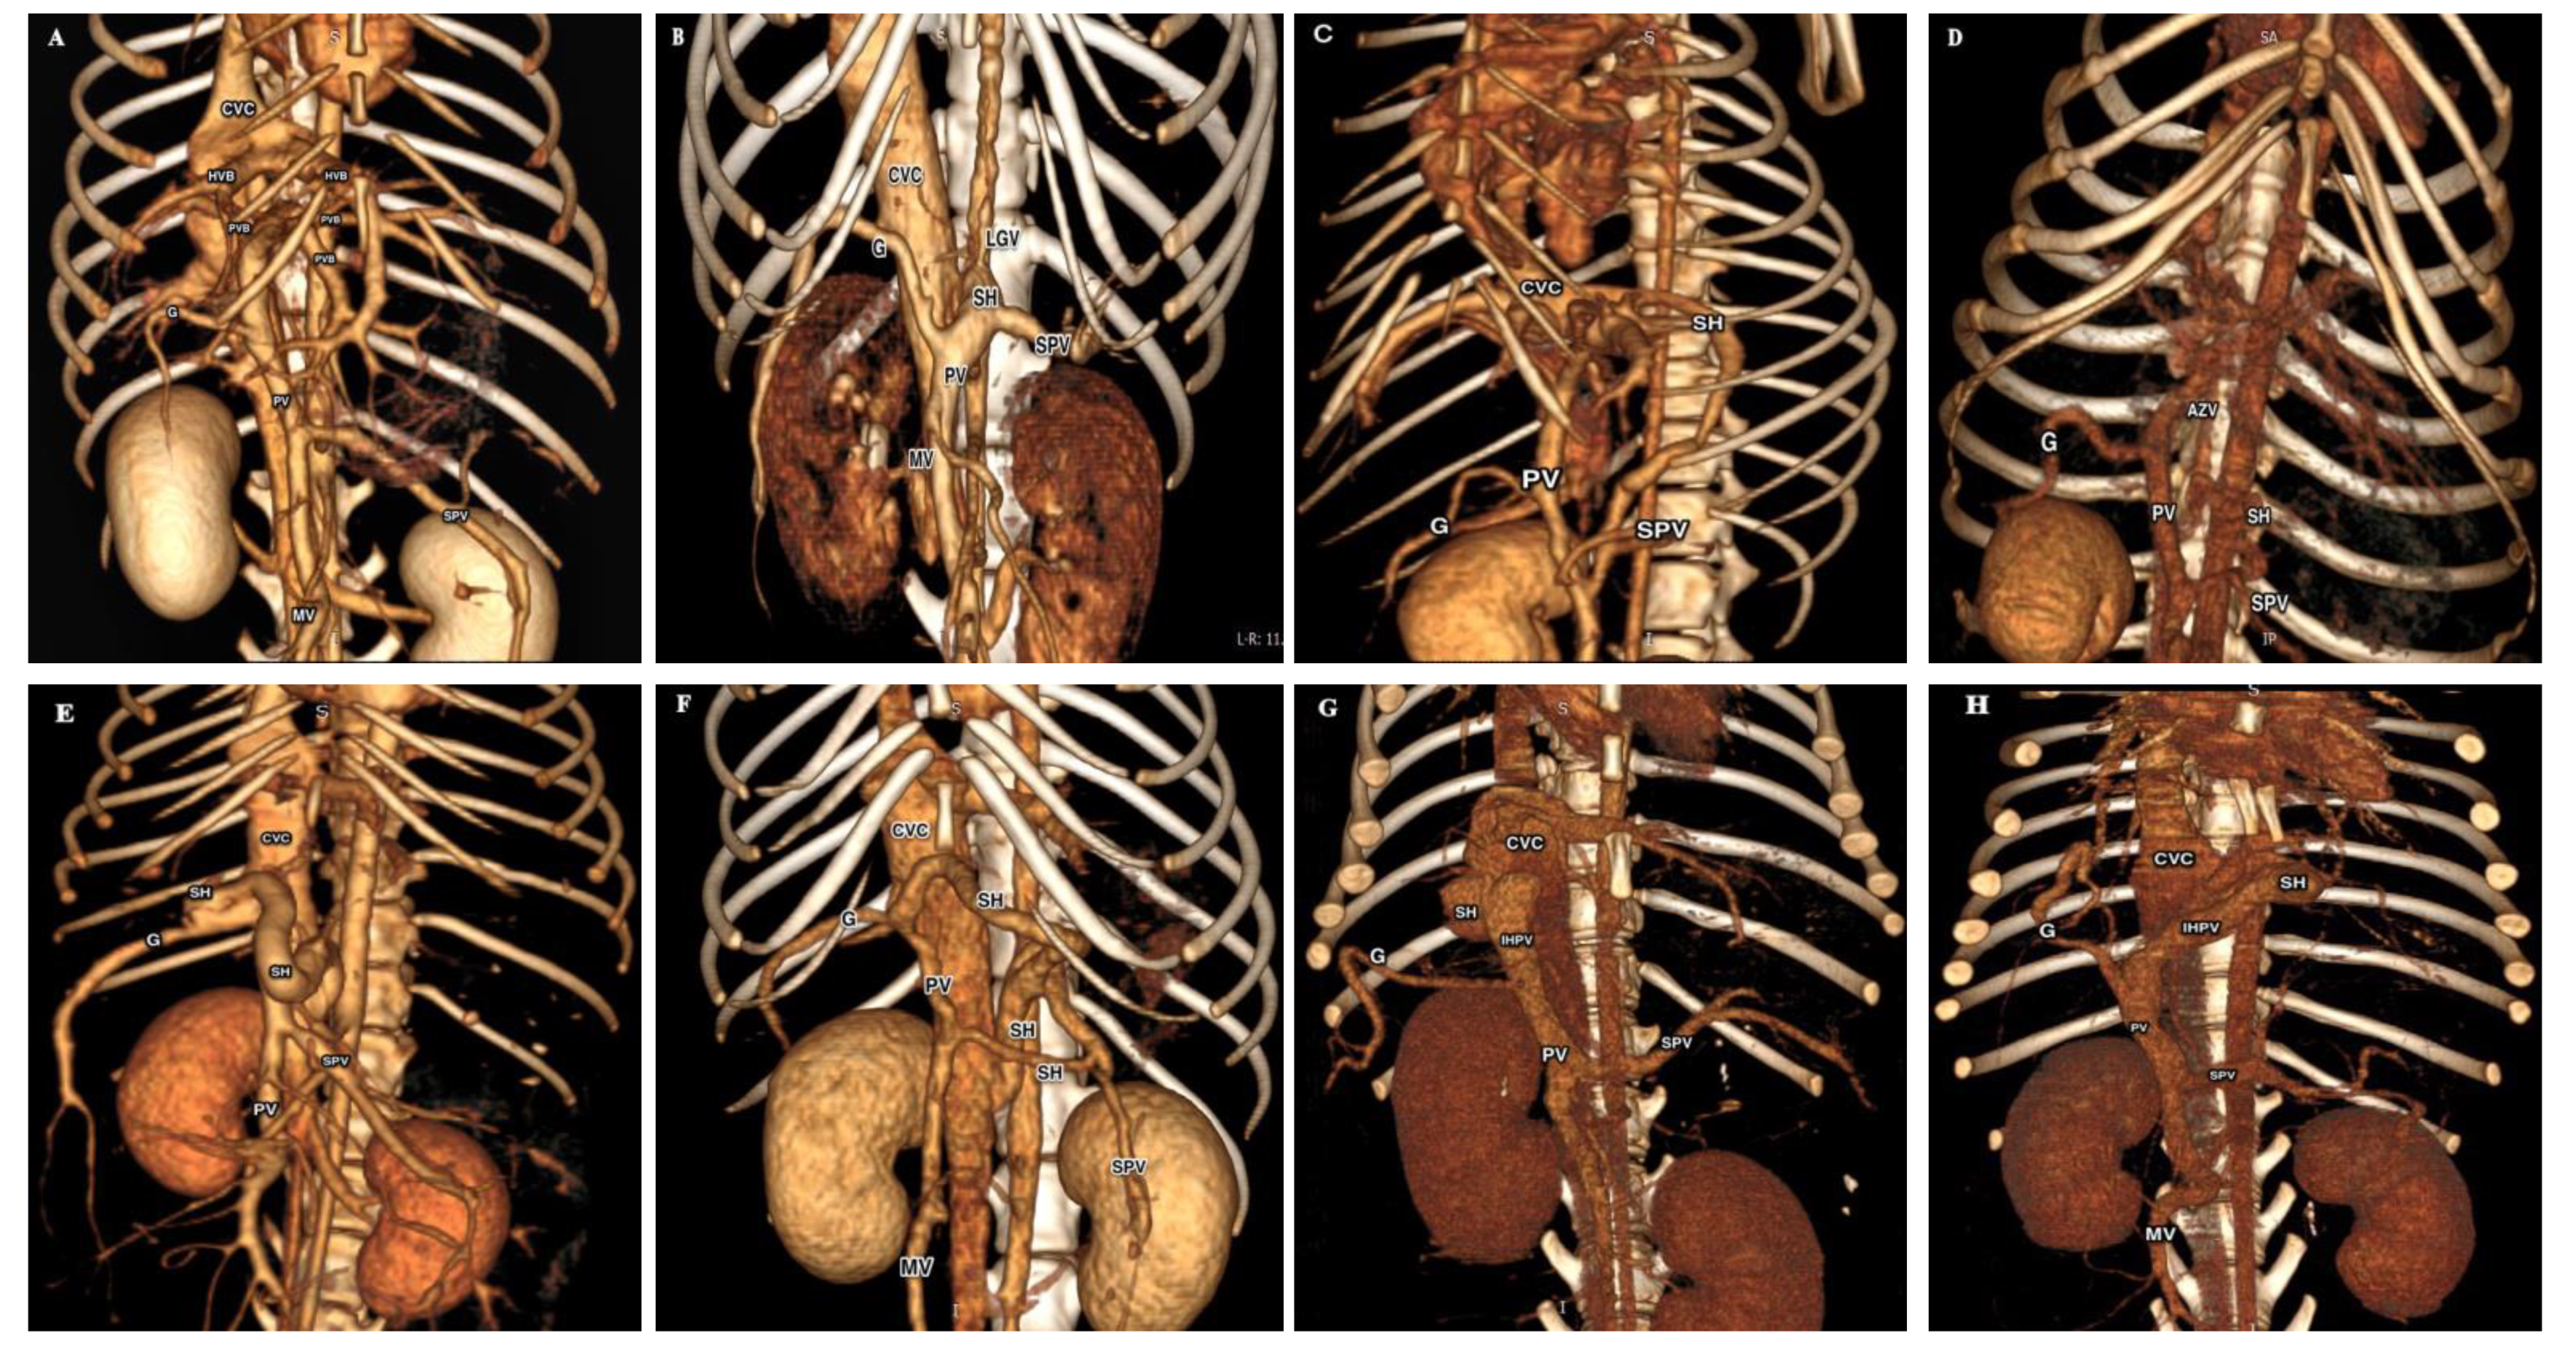

3.3. Histopathological Results

| Microvesicular steatosis | 0 (0%) | 12 (100%) | 8 (66.67%) | 9 (75%) | 10 (83.33%) | 9 (75%) | 12 (100%) | 12 (100%) |

| Macrovesicular steatosis | 0 (0%) | 10 (83.33%) | 0 (0%) | 1 (8.33%) | 9 (75%) | 8 (66.67%) | 4 (33.33%) | 3 (25%) |

| Lipid granuloma | 0 (0%) | 9 (75%) | 0 (0%) | 0 (0%) | 7 (66.67%) | 8 (66.67%) | 2 (16.67%) | 1 (8.33%) |

| Hemosiderin within lipid granuloma or Kupffer cells | 0 (0%) | 11 (91.67%) | 1 (8.33%) | 2 (16.67%) | 10 (83.33%) | 10 (83.33%) | 11 (91.67%) | 12 (100%) |

| Portal veins absence or hypoplasia | 0 (0%) | 12 (100%) | 3 (25%) | 3 (16.67%) | 12 (100%) | 12 (100%) | 12 (100%) | 12 (100%) |

| Arteriolar hyperplasia | 0 (0%) | 7 (58.33%) | 2 (16.67%) | 3 (25%) | 9 (75%) | 8 (66.67%) | 12 (100%) | 12 (100%) |

| Biliary hyperplasia | 0 (0%) | 7 (58.33%) | 2 (16.67%) | 3 (25%) | 9 (75%) | 8 (66.67%) | 12 (100%) | 12 (100%) |

| Fibrosis (portal, periportal and parenchymal) | 0 (0%) | 7 (58.33%) | 2 (16.67%) | 2 (16.67%) | 6 (50%) | 7 (58.33%) | 3 (25%) | 4 (33.33%) |